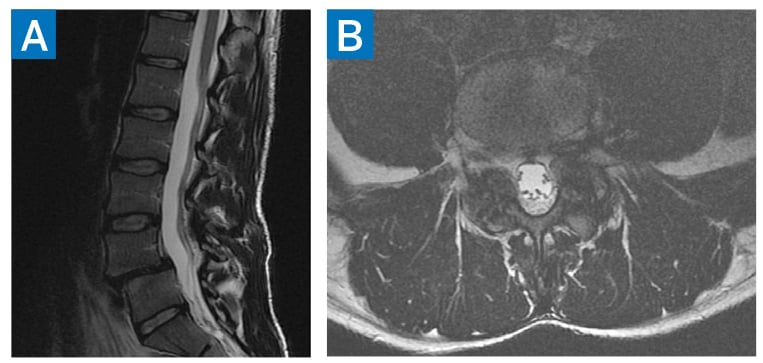

Radiographs of the lumbar spine demonstrated degenerative disc disease at L4–L5, with associated anterolisthesis (Fig. 1). Magnetic resonance imaging (MRI) confirmed Meyerding grade-1 spondylolisthesis at L4–L5 (Fig. 2). Given his progressive symptoms and radiographic evidence of lumbar instability, the patient was indicated for L4–L5 posterior decompression and fusion.

Figure 2: Preoperative MRI at the level of L4–L5 demonstrating spondylolisthesis in sagittal T2 (A) and axial T2 (B) sequences.